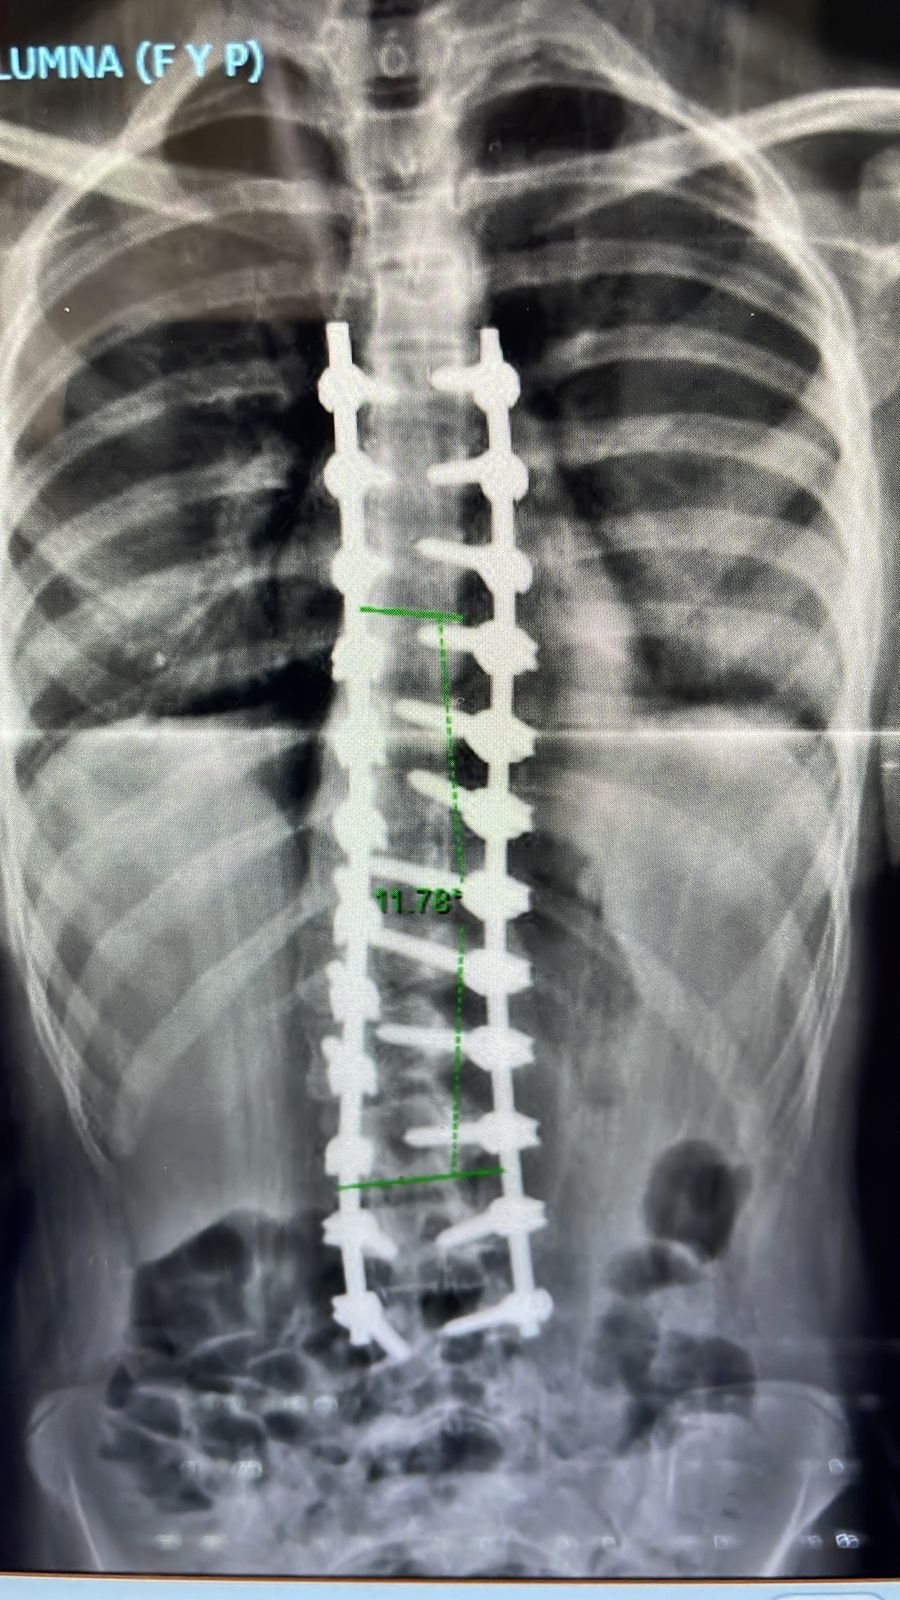

Escoliosis Progresiva.

“ Soy María Mercedes a los 11 años me diagnosticaron escoliosis, empecé con 40 grados, y ya a los 13 llegué a tener casi 70 grados. Me avergonzaba usar remeras ajustadas, practico patín artístico dese los 3 años, y a los 12 había saltos y figuras que no me salían debido a la severidad de la escoliosis .A los 13 años, el 20 de enero del 2022, fui operada por el Dr. Pablo Fiorillo. La operación fue todo un éxito, el Dr. me brindó contención y seguridad en todo momento, súper recomendable. En mayo del 2022, ya retomaba mi deporte patín artístico. Durante todo el año 2023 seguí realizando patín artístico y competencia individual, pudiendo participar en campeonatos regionales y provinciales. Gracias a la excelencia profesional del Dr., hoy con 15 años puedo llevar una vida normal y seguir patinando”